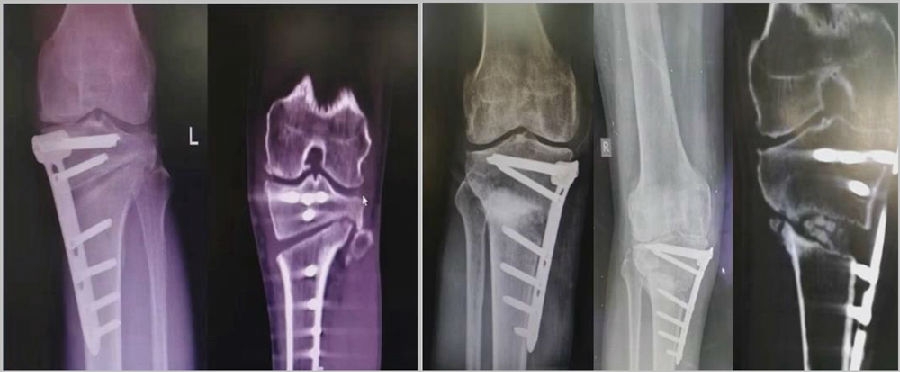

(2)Ⅱ型骨折

当出现Ⅱ型骨折时要特别注意,因为此时截骨的远端就是骨折的远端,近端只有上胫腓周围骨筋膜存在,所以相对来说Ⅱ型骨折并不稳定。

首先用拉力螺钉复位,调整好力线。然后做结构性植骨,延迟负重,所谓延迟负重就是延迟到外侧合页和上行截骨线处达到初始愈合,然后再让患者进行负重。如果不做结构植骨加延迟负重,就会出现一些非常严重的现象,如不愈合。

拉力钉复位,结构性植骨

左侧患者未植骨正常负重,术后4个月不愈合;右侧患者非结构性植骨过早负重,术后1年未愈合